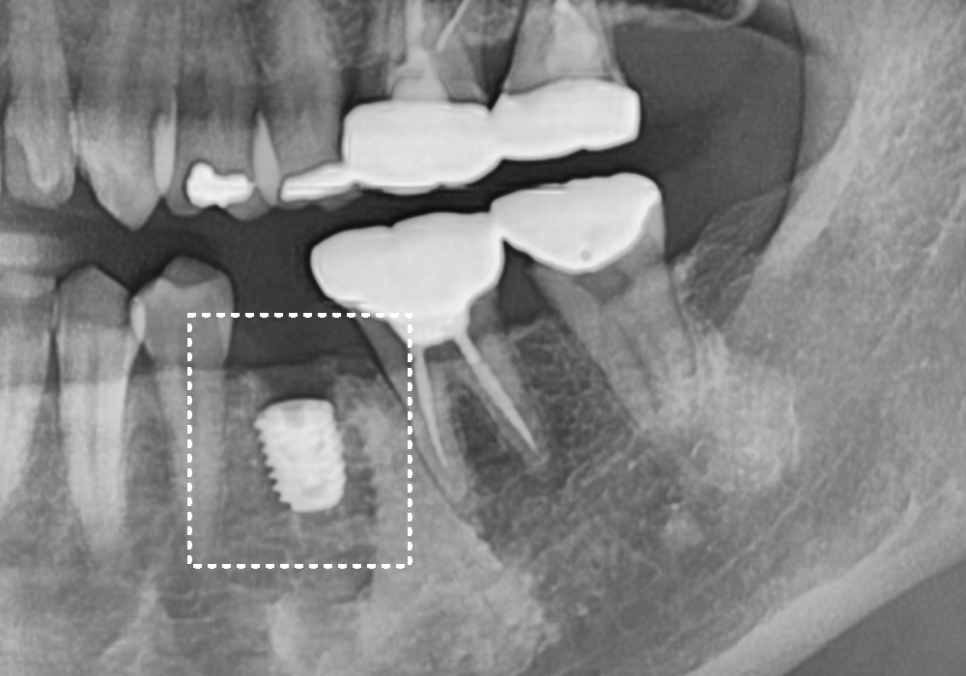

다행히 뿌리 쪽에 염증이 번지지 않은 상태라,

치아를 뽑은 당일에 바로 임플란트를 심는

'발치 즉시 식립'을 진행했습니다.

241108

신경관과 충분한 거리를 두면서

가장 이상적인 위치에 알맞게 심어진 것을

확인할 수 있었죠.

그로부터 5개월 뒤, 임플란트가 뼈와 단단하게

자리를 잡은 것을 확인하고

최종 보철 단계에 들어갔습니다.